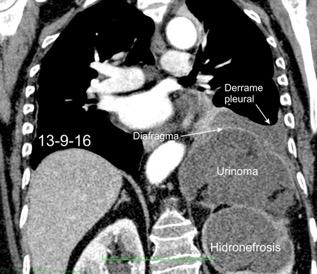

27. DERRAME PLEURAL IZQUIERDO. URINOMA

Enfermedad subdiafragmática Urinoma

Raro. Trasudado.

Orina en espacio pleural

Causas en 78 casos

Trauma……..66

Postcirugía 16

Obstrucción…21 aguda con cálculo e hidronefrosis..12

Freitas A et al. Pleural Effusion Secondary to Obstructive Uropathy: A Case of Urinothorax. Eur J Case Rep Intern Med. 2020/ Toubes ME et al. Urinothorax: a systematic review. J Thorac Dis 2017;

Hidronefrosis con cálculo ureteral